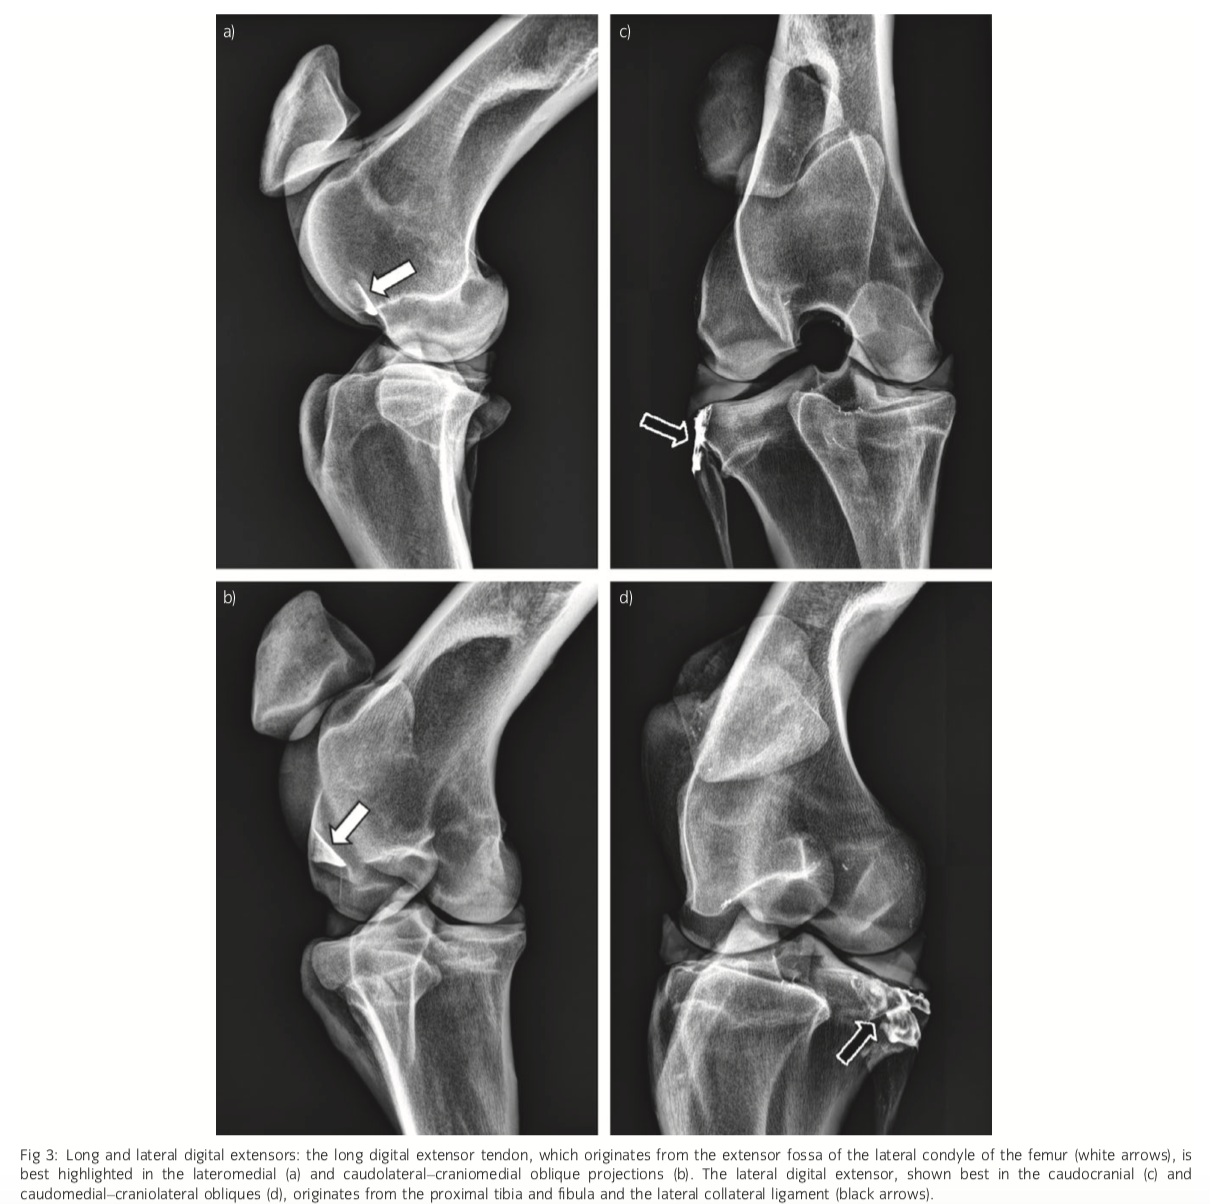

Long extensor origin

Extensor fossa of the lateral femoral condyle

Lateral extensor origin

Proximal tibia/head of fibula and lateral collateral insertion